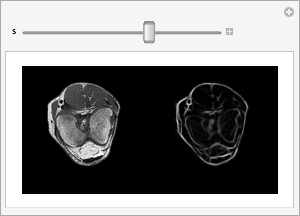

A ridge filter highlights voxels with a high main principal curvature in the intensity distribution. This, for example, applies to fascia in between muscle tissue.

Side-by-side rendering of each slice of the original and filtered knee volume.